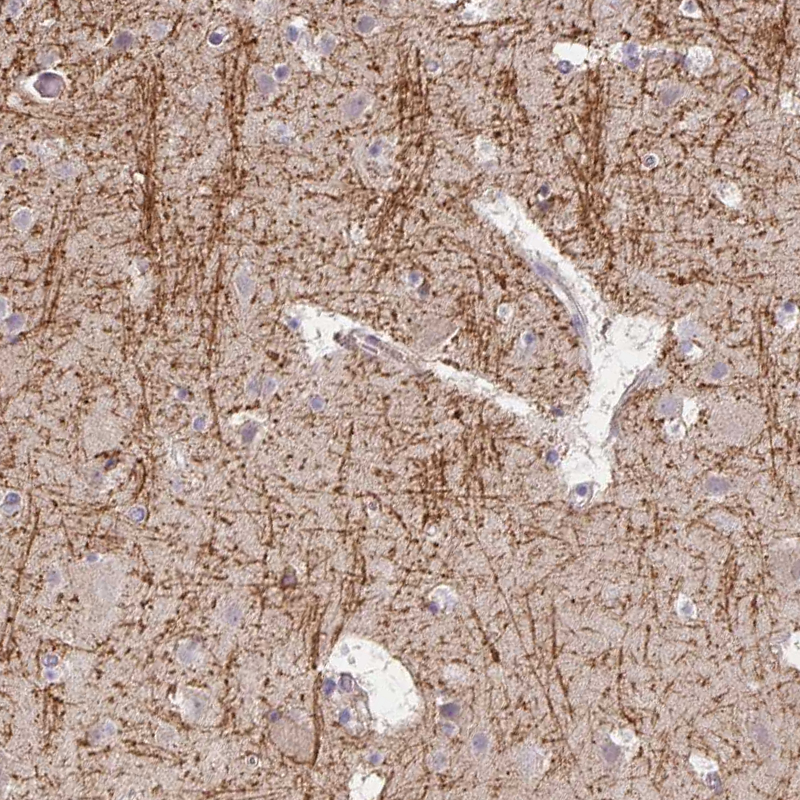

Immunohistochemical staining of human cerebral cortex shows strong positivity in neuronal processes in neuropil.